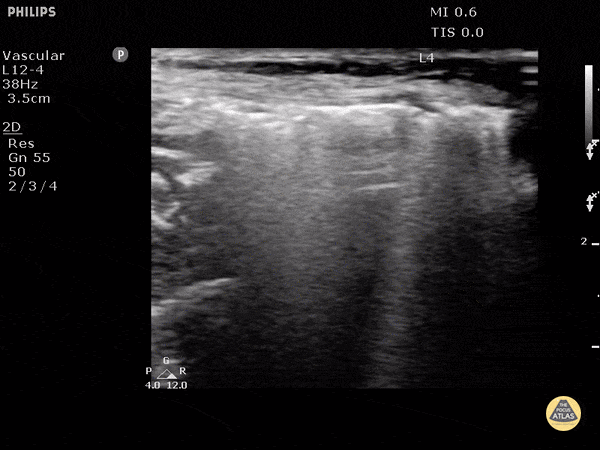

Soft Tissue - Subcutaneous Emphysema

Air poorly transmits ultrasound waves and when fluids or solids interface with air, they lead to echogenic irregularities with comet tails that can often obscure the tissue behind it. Dr. Justin Bowra et al.